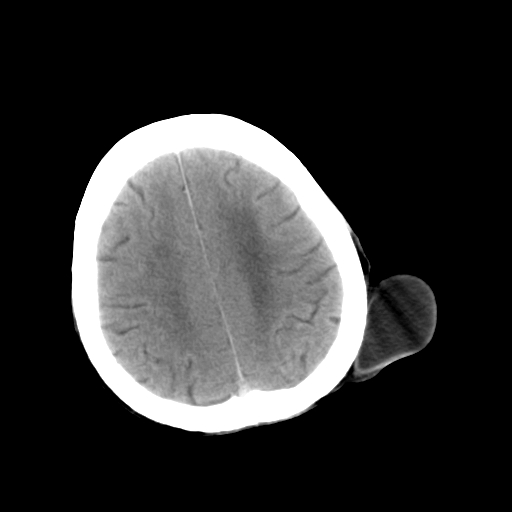

标题: CT25147:男,62岁,右侧肢体活动障碍不灵活三天。 [打印本页]

男,62岁,右侧肢体活动障碍不灵活三天,左侧头皮肿物十余年(ct值8hu)。

1)多发性腔隙性脑梗塞。2)脑白质病。3)脑萎缩。4)左侧枕顶部头皮下皮样囊肿,不排除脂肪瘤。

1)多发性腔隙性脑梗塞。2)脑白质病。3)脑萎缩。4)左侧枕顶部头皮下皮样囊肿或表皮样囊肿。